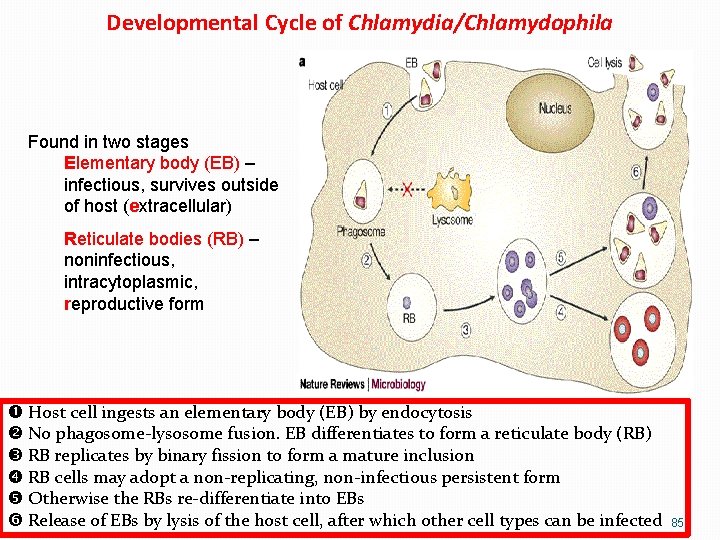

Developmental Cycle of Chlamydia/Chlamydophila Found in two stages Elementary body (EB) – infectious, survives outside of host (extracellular) Reticulate bodies (RB) – noninfectious, intracytoplasmic, reproductive form Host cell ingests an elementary body (EB) by endocytosis No phagosome-lysosome fusion. EB differentiates to form a reticulate body (RB) RB replicates by binary fission to form a mature inclusion RB cells may adopt a non-replicating, non-infectious persistent form Otherwise the RBs re-differentiate into EBs Release of EBs by lysis of the host cell, after which other cell types can be infected 85